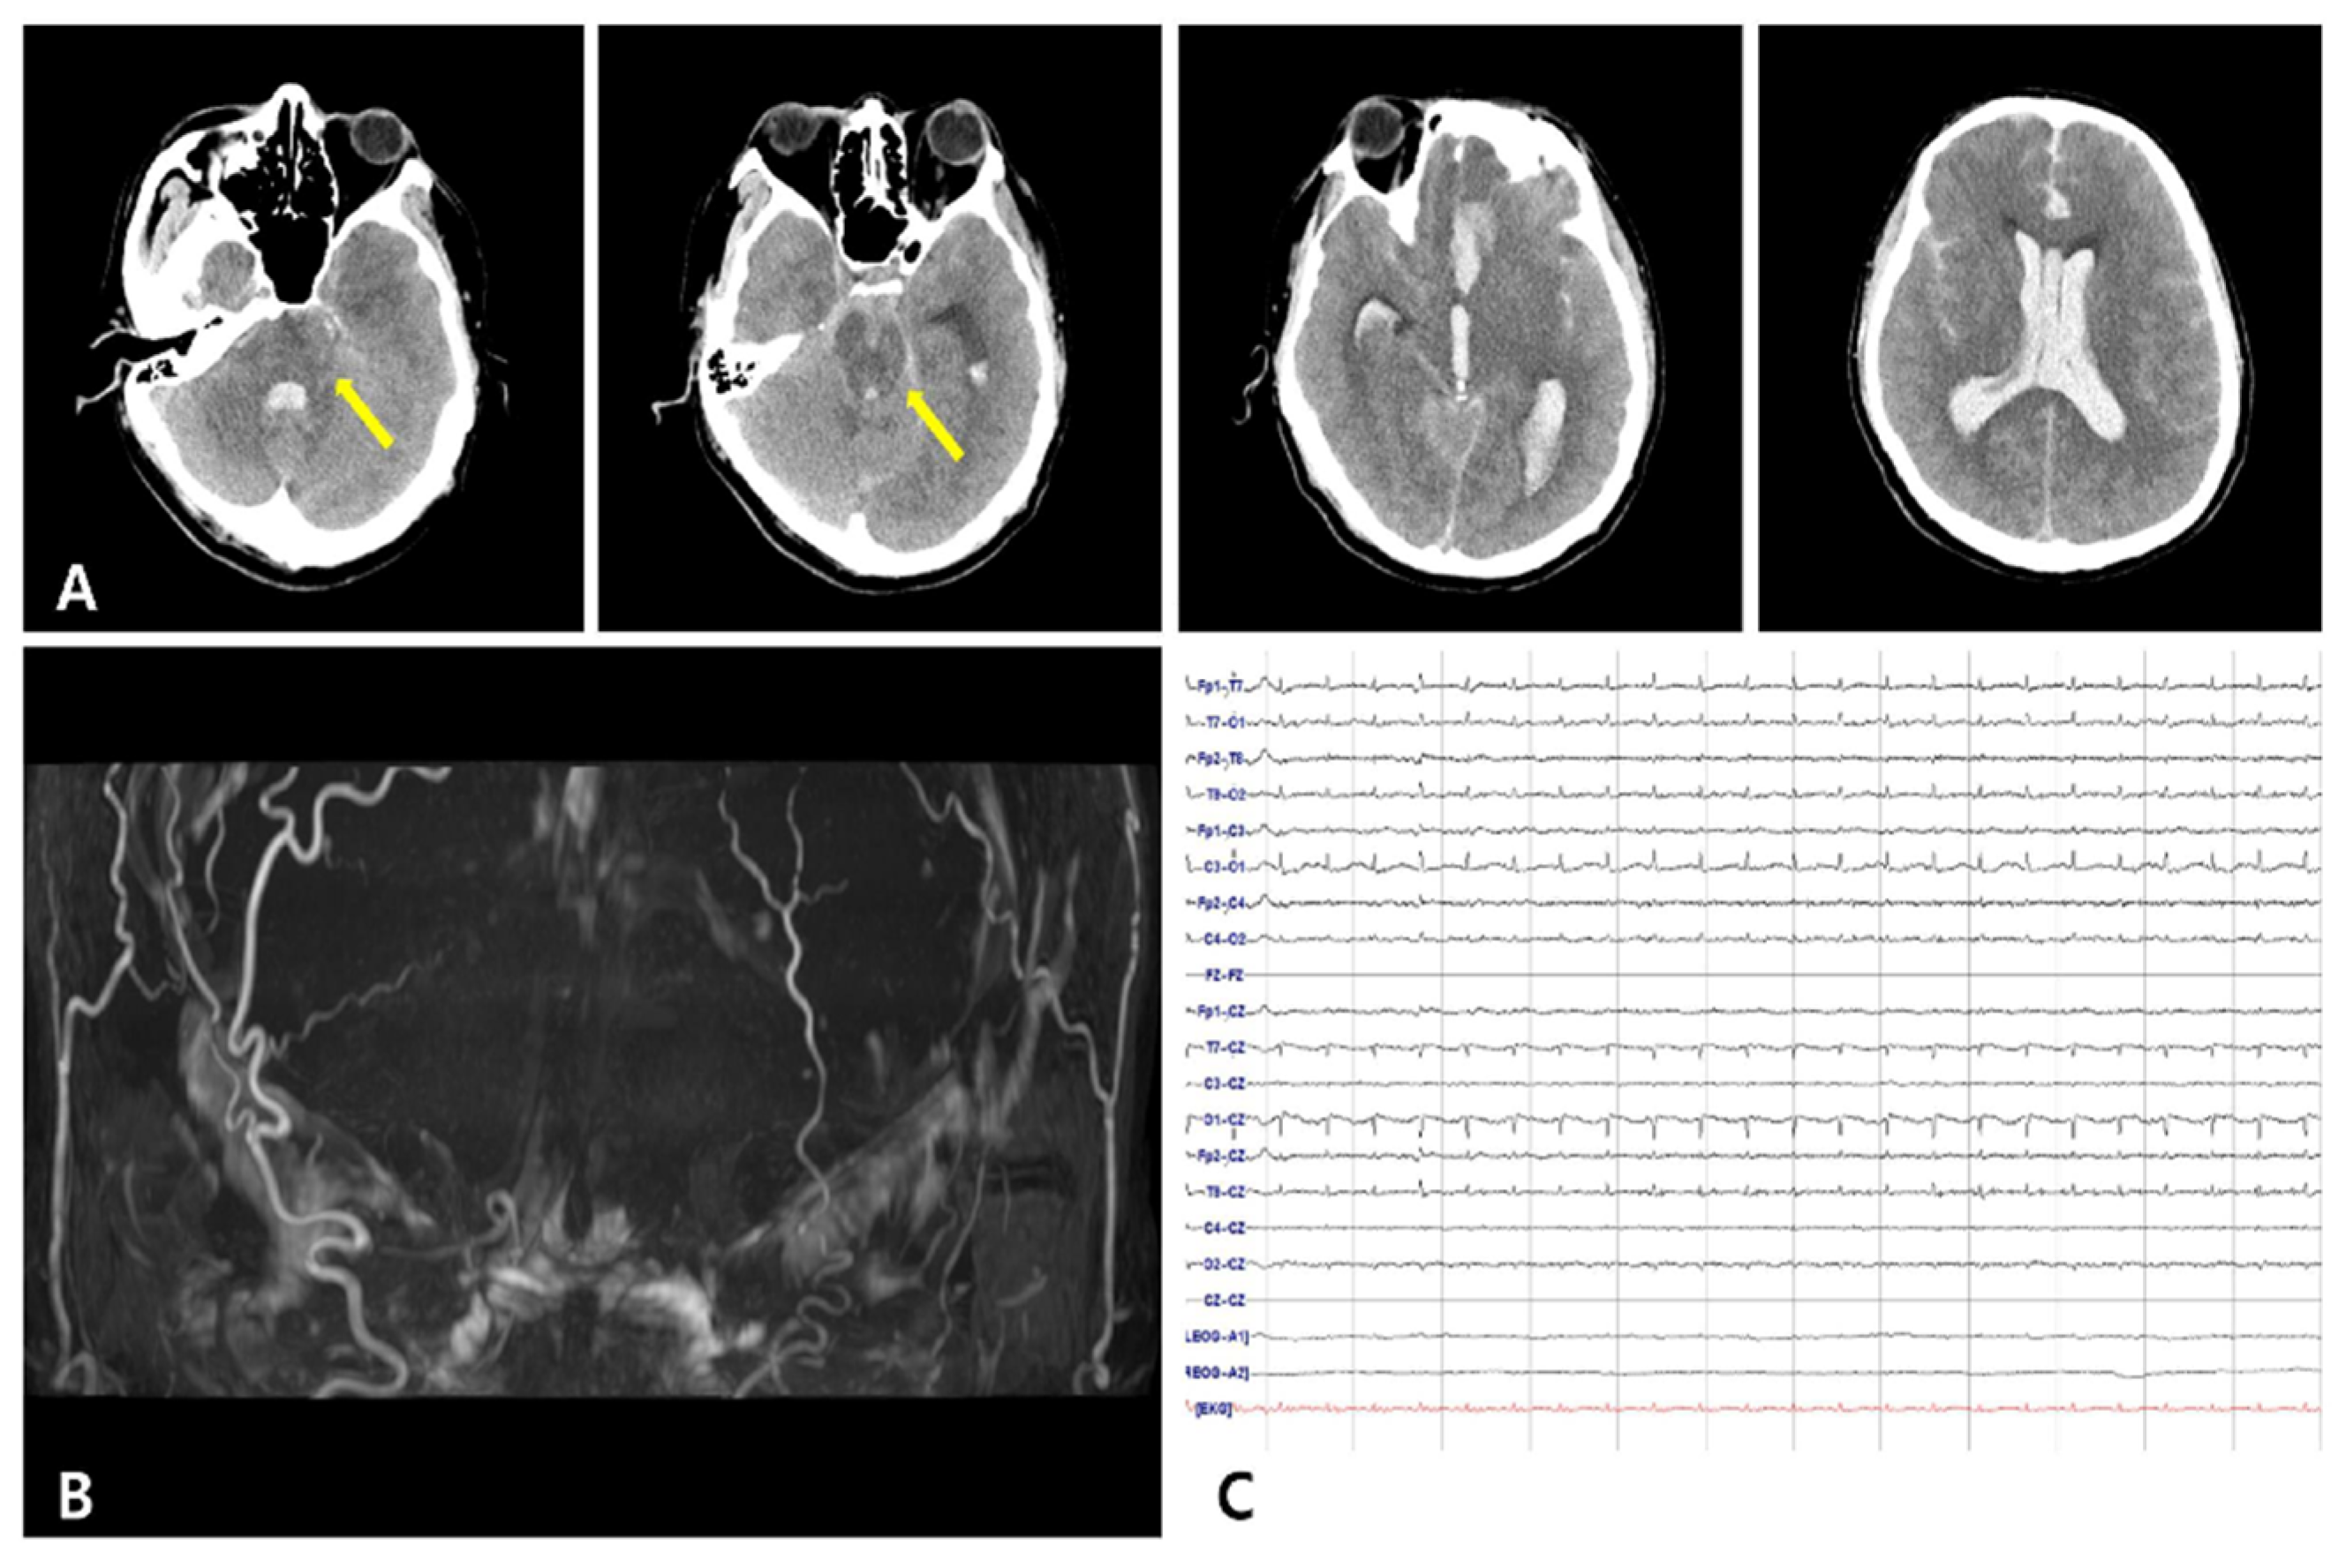

A 41-year-old man with a history of liver cirrhosis over 10 years, who had vomited and lost consciousness in a car in front of a factory, was transported to the emergency room. On admission, he was in a semicomatose state, and his Glasgow Coma Scale score was 4. Brain computed tomography performed within 10 minutes of his arrival showed intracerebral hemorrhage in his frontal lobe, intraventricular hemorrhage, and subarachnoid hemorrhage throughout his brain, including the basal cistern (Figure 1A). The Modified Fisher Score was 4 and the Hunt–Hess grade was 5. The patient fell into a coma on the ninth day of admission and lost his pupillary reflex, corneal reflex, oculo-cephalic reflex, vestibulo-ocular reflex, cilio-spinal reflex, gag reflex, and cough reflex. The intracerebral artery was not observed in brain magnetic resonance angiography (Figure 1B), and electroencephalography showed electrocerebral silence even at 2 µV/mm sensitivity (Figure 1C). During the neurological examination to determine brain death, the brain-stem reflex was not observed. However, when the left sole of his foot was stimulated, a reflex movement of the skin was subtended by a muscle contraction of the medial part of the left thigh (middle third and lower third). The visible contraction can be attributed to the gracilis muscle (Supplementary Video). No other spinal reflex was observed.

Figure 1. Radiologic findings and electroencephalography of the patient. (A) Brain computed tomography shows intracerebral hemorrhage in the left frontal lobe and massive intraventricular hemorrhage with subarachnoid hemorrhage including the basal cistern. Hypodense lesions in the brain stem were observed due to hypoxic brain damage (arrow). (B) Brain magnetic resonance angiography of the patient shows no cerebral blood flow. (C) There is no identifiable cerebral activity in any lead throughout the recording, even at 2 µV/mm sensitivity.